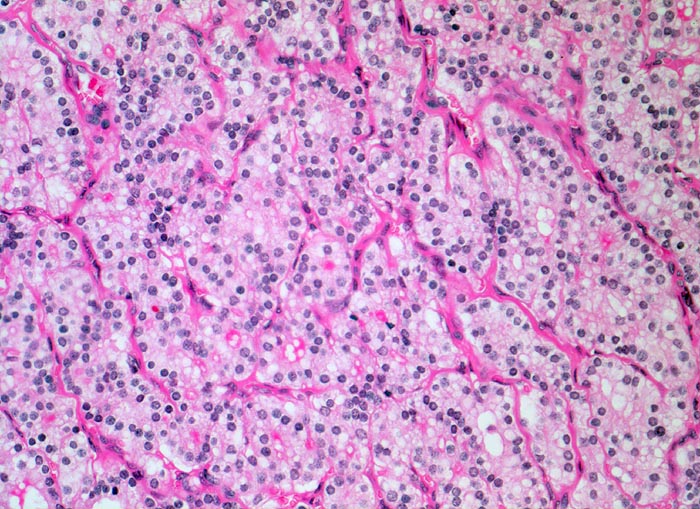

PathoPic – image database / PathoPic ID 4841 - autonomes Adenom

autonomes Adenom

Schilddrüse

Die Follikel des endokrin aktiven Adenoms enthalten nur sehr wenig oder gar kein Kolloid. Die Zellen sind kubisch bis hochprismatisch und vielfach mehrreihig angeordnet.

Histologie

200